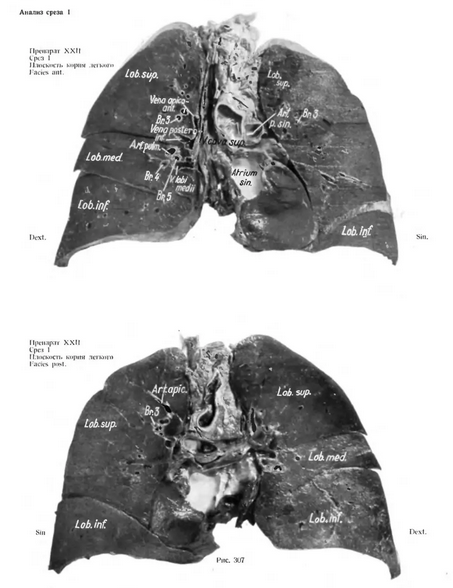

АНАЛИЗ ПРЕПАРАТА XXII Ввиду того, что для доказательства правильности наших утверждений, касающихся характерной плоскости ворот легкого, недостаточно рассмотреть один препарат, мы приводим также препарат XXII. Две рентгенограммы этого сердечно-легочного препарата уже приводились при обсуждении бронхиальной плоскости (рис. 107а, б), причем проводилось сравнение рентгенограммы бронхиальной системы с рентгенограммой неповрежденного сердечно-легочного препарата или с рентгенограммой среза толщиной 1,5 см, проходящего через характерную плоскость. В дальнейшем дается сравнительный анатомический и рентгенологический анализ трех срезов, изготовленных из препарата бронхиальной плоскости или плоскости ворот легкого. Упомянутые три среза находятся таким образом в трех параллельных плоскостях. Срез 1 В сердечно-легочном препарате срез проводился непосредственно вентрально от плоскости ворот легкого, так что самое поверхностное образование — truncus superior venae pulmonalis dext. — уже

Срез 1

В сердечно-легочном препарате срез проводился непосредственно вентрально от плоскости ворот легкого, так что самое поверхностное образование — truncus superior venae pulmonalis dext. — уже находится в срезе. Из элементов средостения в срез попали следующие : V. cava superior, части правого предсердия, левый желудочек, далее мышцы левою предсердия и сердечное ушко. Видны главный ствол art. pulmonalis и начальная часть правой ветви.

В избранной плоскости представлены все доли на большем или меньшем протяжении.

Приведенная схема составлена на основании анализа анатомической картины и рентгенограммы, легочные вены отмечены пунктиром, легочные артерии заштрихованы, бронхи нанесены контуром.

Резюмируя, можно сказать следующее. Плоскость среза не имеет точно фронтального направления ; из элементов ворот левого легкого, которые в общем лежат несколько дорзальнее ворот правого легкого, можно видеть лишь часть венозного ствола, располагающегося кпереди от левого верхнедолевого бронха. Из главных элементов ворот правого легкого в данном срезе находится только правый верхний truncus w. pulmonalis.